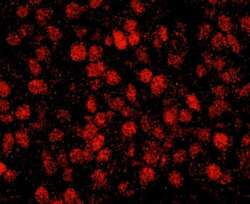

- Submitted by

- LSBio (provider)

- Enhanced method

- Genetic validation

- Main image

- Experimental details

- Detection of Human RCOR3 by IHC-IF. Sample: FFPE section of human breast carcinoma. Antibody: Affinity purified rabbit anti-RCOR3 used at a dilution of 1:100. Detection: Red-fluorescent goat anti-rabbit IgG highly cross-adsorbed Antibody used at a dilution of 1:100.

- Submitted by

- LSBio (provider)

- Enhanced method

- Genetic validation

- Main image

- Experimental details

- Detection of human RCOR3 by immunohistochemistry. Sample: FFPE section of human breast carcinoma. Antibody: Affinity purified rabbit anti-RCOR3 used at a dilution of 1:100. Detection: Red-fluorescent goat anti-rabbit IgG highly cross-adsorbed Antibody used at a dilution of 1:100.